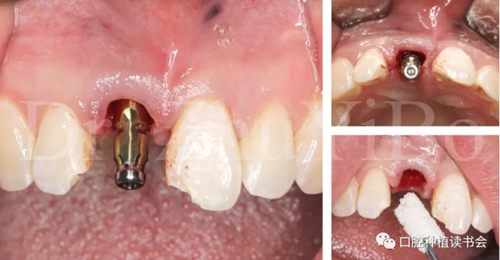

4.2.3 植入Nobel active種植系統(tǒng) RP 13mm種植體,植入扭矩大于45Ncm,初期穩(wěn)定性良好(圖11、圖12))。

圖11 使用Nobel active手用植入扳手精確控制植入方向

圖12 種植體初期穩(wěn)定性良好,注意與唇側(cè)骨板間的間隙

4.2.4取模,制作臨時(shí)修復(fù)體(圖13)。

圖13 一定要在植骨前,進(jìn)行取模,有多種方法可以選擇

4.2.5 雙區(qū)植骨,戴牙(圖14,圖15)。

圖14 雙區(qū)植骨需要植到齦緣水平